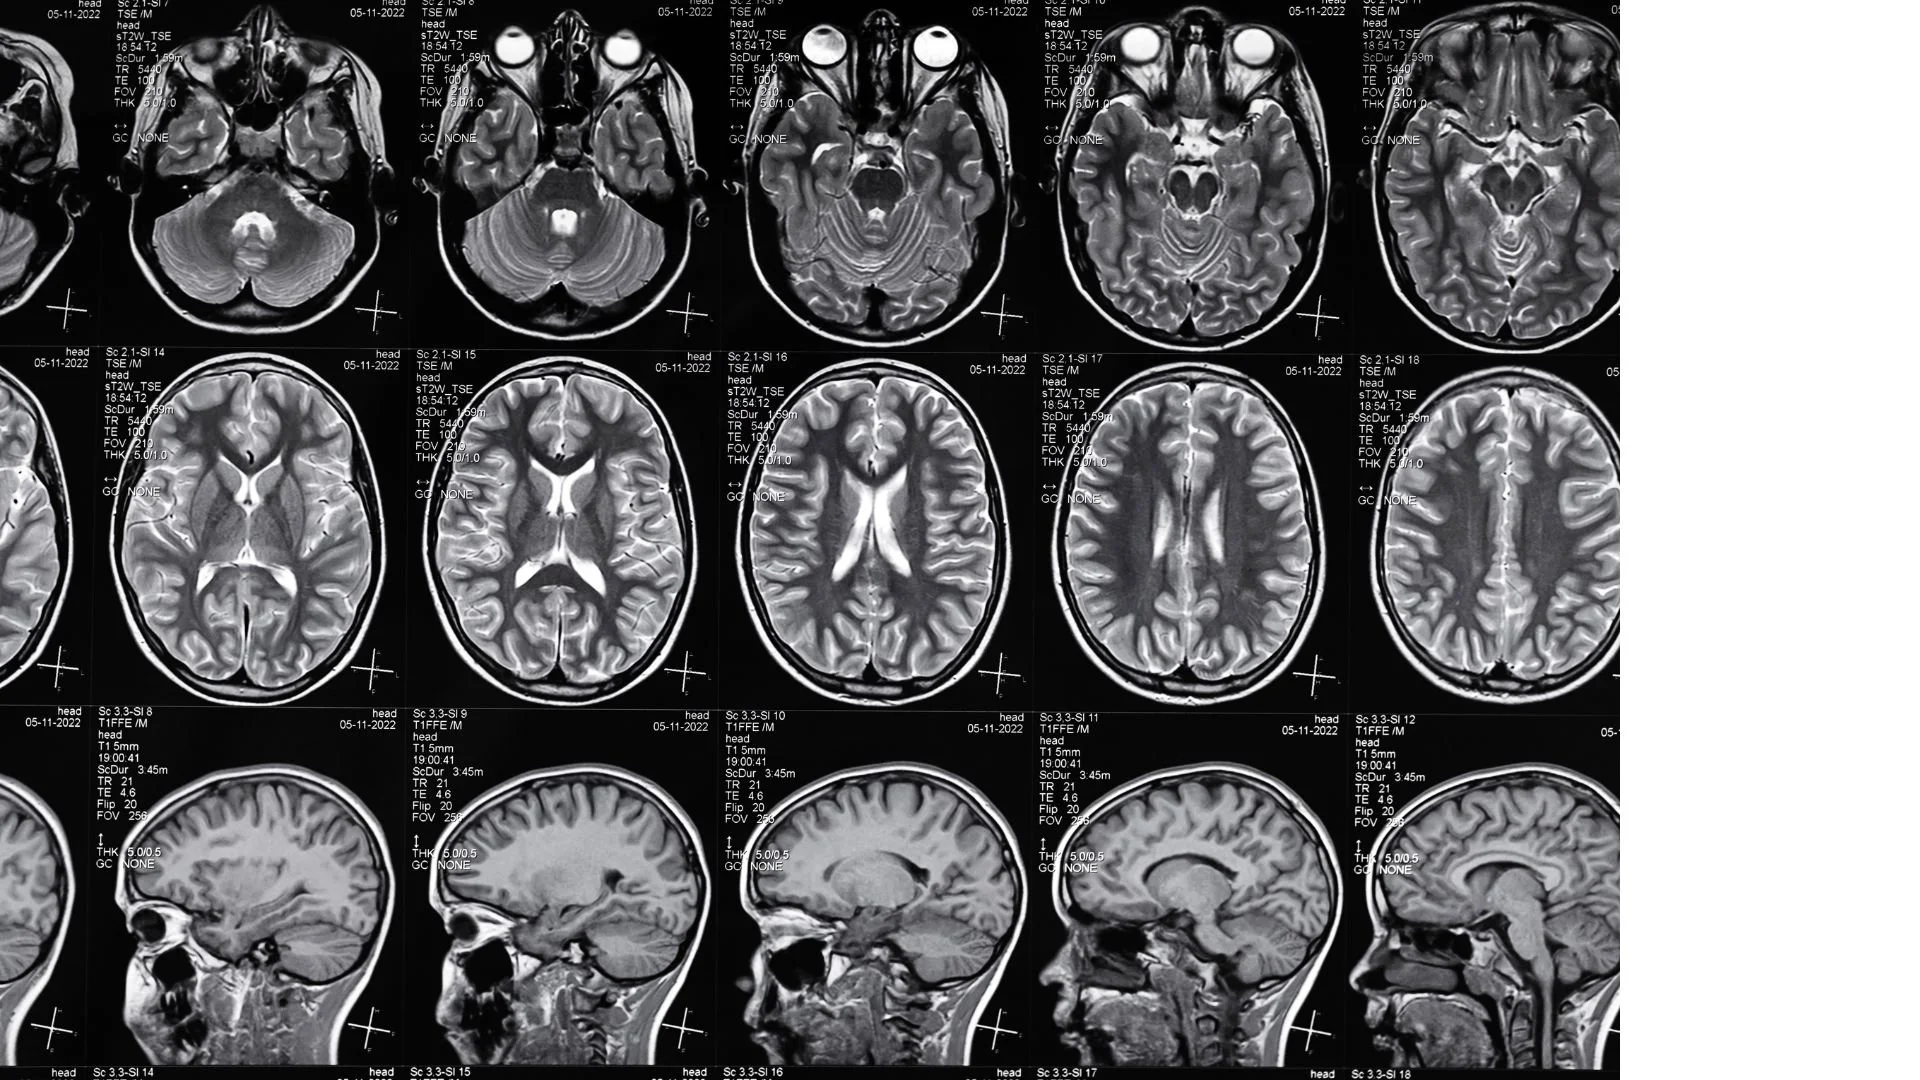

A series of MRI brain scans displayed in multiple rows and columns, showing different cross-sectional views of the brain in black, white, and gray tones.